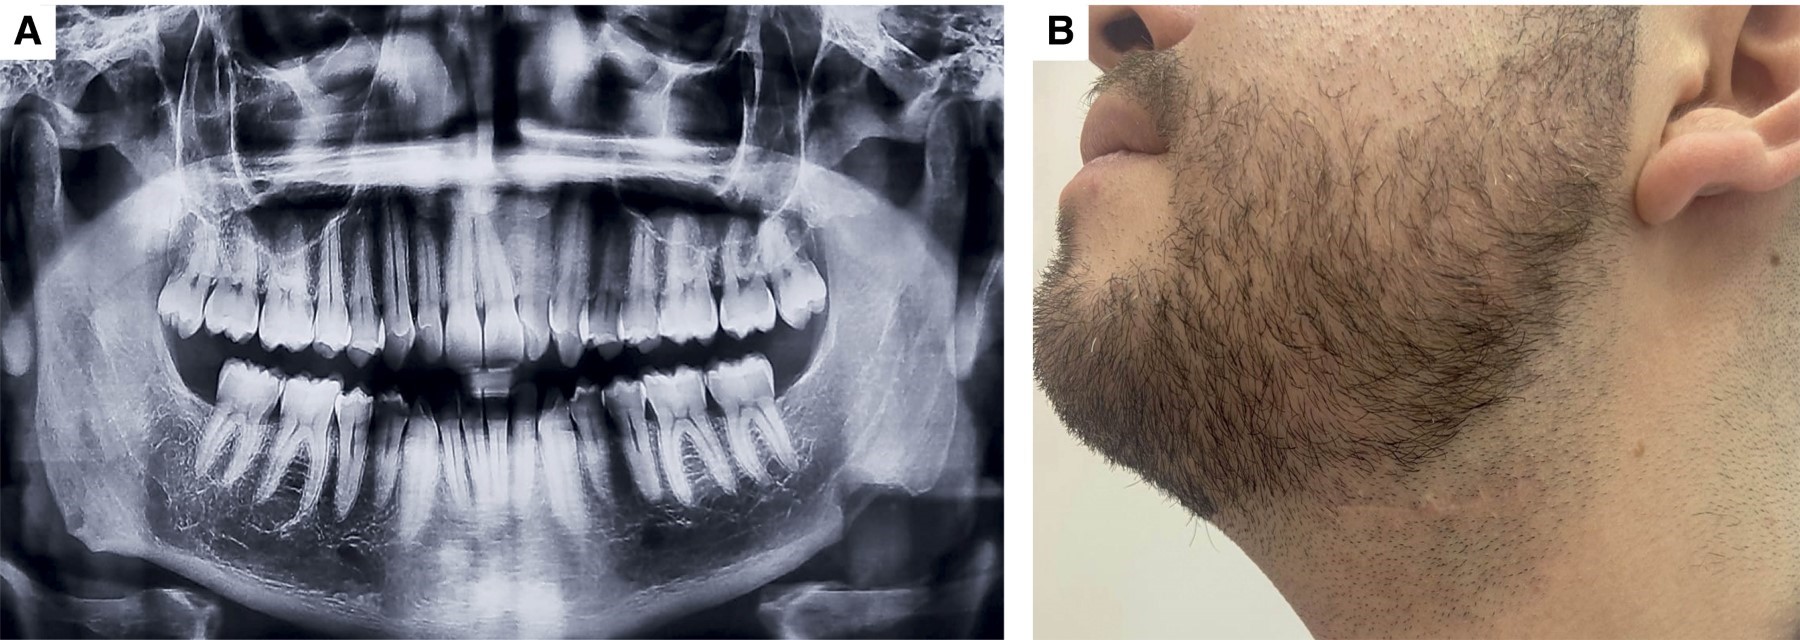

Acude a consulta odontológica donde se solicita la toma de una ortopantomografía de control en la que se identificó una zona radiopaca homogénea de aproximadamente un centímetro de diámetro localizada en la cortical basal de la mandíbula del lado izquierdo, próxima al ángulo mandibular; de aspecto lobulado con bordes bien definidos, asintomática, que pasa desapercibida extraoralmente, de tiempo de evolución desconocido (Figura 1A). Después de tres años refirió crecimiento de la lesión previamente descrita y se realizó nuevamente la toma de estudios de imagen donde se confirmó el aumento de tamaño (Figura 1B). Ante los cambios presentados se decidió realizar la exéresis de la misma bajo el diagnóstico presuntivo de odontoma complejo (Figura 2A). El abordaje se llevó a cabo bajo anestesia general balanceada; previo marcaje quirúrgico para delimitar referencias anatómicas de importancia, infiltración de lidocaína con epinefrina 72 mg/36 μg realizando abordaje tipo Risdon, posterior disección a cuerpo y ángulo mandibular izquierdo. Se procede a la exéresis del tejido (Figura 2B), se verifica hemostasia y cierre del abordaje. Concluye procedimiento sin incidencias ni complicaciones. El espécimen consistió en un fragmento único de tejido duro de 2.5 × 2.3 × 2.2 cm, de forma oval, superficie lobulada, color café claro y consistencia dura (Figura 3).

A la valoración postquirúrgica, después de seis meses del procedimiento, el paciente se encuentra asintomático. En la ortopantomografía de control sólo se observan cambios postquirúrgicos de la resección (Figura 5).

De acuerdo con su localización, pueden clasificarse en periféricos o centrales, siendo esto determinado a su ubicación en el hueso afectado, aquellos que se originan a nivel de la cortical o superficie ósea son clasificados como osteomas periostiales, periféricos o exofíticos y a nivel intramedular denominados osteomas endosteales o centrales.1 La mayoría de veces es una entidad detectada radiográficamente. En el presente caso, fue detectado en un inicio por radiografía, pero con el tiempo, el aumento de tamaño de la lesión fue percibido por el paciente (Figura 1B). En relación con la localización de esta entidad, en el ángulo mandibular y periférico,8 realizaron una revisión de todos los casos de osteomas que afectan el ángulo mandibular, encontrando 32 casos reportados en la literatura inglesa y de los casos de esta revisión junto al presente caso, al realizar la estadística descriptiva, especialmente de los datos clínicos-demográficos de la población afectada (Figura 6), se muestra una mayor prevalencia en el sexo masculino, desde los ocho a los 68 años con una media de 36 años; en relación a los datos clínicos se presenta con mayor frecuencia en la zona del ángulo mandibular del lado izquierdo, con aumento de volumen o asimetría del lado afectado y asintomático; si presenta sintomatología clínica, se ha descrito dolor, disfagia y dificultad al tragar. Con lo anterior, se demuestra que el presente caso descrito posee todas las características clínico-demográficos prevalentes en esta entidad, inclusive, en el presente caso, el osteoma se presenta en el ángulo mandibular, el cual su osificación en esta parte mandibular es de tipo intramembranosa.7-9

Figura 2